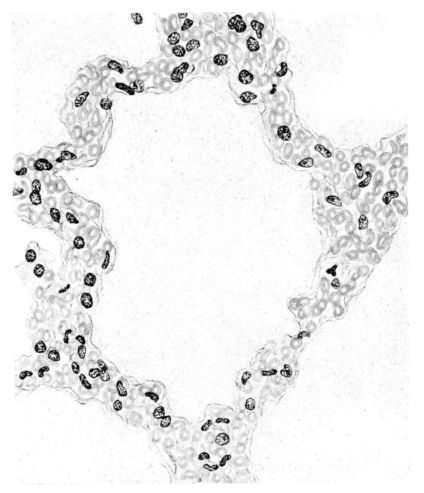

FIG. V. AUTOPSY NO. 95. AN EARLY LESION OF THE BRONCHIOLE CHARACTERIZED BY HYALINIZATION OF THE EPITHELIUM AND SEROUS EXUDATE IN THE LUMEN.

15There is considerable evidence to support the view that the disease spreads from bronchus to bronchus, and in keeping with this view, various stages in the inflammatory processes are more readily determined in these smaller structures than in the trachea. Furthermore, it must be emphasized that even the mildest and the most extreme of these stages are not infrequently encountered in the same lung. The earliest lesion is manifested by an increased homogeneity of the protoplasm of the epithelial lining of the bronchus. The cell protoplasm loses its normal granulation and the nucleus, somewhat darker than usual, becomes conspicuous on a red base (Fig. V). In the lumen of such a tube a serous exudate, perhaps mixed with mucus, is encountered, and there is some spreading apart of the surrounding muscular tissue with engorgement of the vessels. This picture merges gradually into one where the epithelium appears as a homogeneous, red-staining ribbon, devoid of nuclei, often exfoliated, in part at least, from the underlying submucosa (92). The change is traceable through the larger bronchi, even to the ducti alveolares, and not infrequently, bacteria, either as a diffuse, minute dotting or in the form of circumscribed, colony-like formations, are spread through the red, ribbon-like strand (Fig. XVI). With the exfoliation of the epithelial lining, the submucous vessels become more and more conspicuous and may bulge into the lumen of the tube (Fig. VI). That they actually weep into the lumen is proved by the presence of red blood cells in the exudate, now rich in mucus, broken-down nuclei, and desquamated cells. The necrotizing process may not extend deeper than the epithelial lining as is the status described above (140, 162), but it also frequently involves the underlying submucous and muscular layers, so that these lose their identity and stand out as homogeneous masses, in which fragmented nuclei and bacterial accumulations are prominent. Such deeper necrotizing areas may be focal (Fig. VII), or may involve the entire circumference of the tube (Fig. VIII). Occasionally, the epithelium, now dead and staining homogeneously, is lifted from the underlying submucosa in the form of a blister (66), and has very much the same appearance as the well known, early reaction which follows the application of croton oil to the rabbit’s ear. Where this occurs, the submucosa is less involved, as though the necrotizing agent had not penetrated to the same depth and the serous reaction beneath were actually a beneficent exudate. These blisters are in contrast with the deeper areas where the fibrinous mass, mixed with the dead tissue, forms an intensely staining ring or band, which extends through the bronchiolar wall even to the surrounding alveoli.

A more striking picture, however, even than this aplastic alveolar exudate appears in the terminal bronchioles. In many instances, these are conspicuous on account of their size, for they are dilated to form prominent, often irregular, sacs (Fig. XV). The distention of these terminal bronchioles may be so great that the surrounding alveoli are compressed. What makes them even more conspicuous is their lining, once epithelium, but now a swollen, thick, homogeneously staining material, with complete loss of architecture; the material forms (with hematoxylin and eosin) a red band limiting the lung tissue and sharply demarcating it from the exudate within the bronchioles (48, 92). However, this ribbon of red, often thickened by fibrin deposition, is not always pure, for bacteria thrive in the dead tissue. They occur singly, paired, in chains, and also as circumscribed, dense masses which in size and position, simulate nuclei (162) (Fig. XVI). This same hyalinization of the epithelium, it will be recalled, occurs in the larger bronchi (Fig. V), and there, too, bacteria frequently develop in the dead tissue (Fig. VIII). In the smallest bronchiolar ramifications, acute epithelial necrosis is not infrequently encountered, even when the surrounding lung tissue is relatively normal (Fig. XVI). That the process does not stop with the epithelium, but, as in the larger bronchi, may extend through the entire structure of the bronchioles, is manifest. Even the alveolar walls may be involved and frequently homogeneous pink or red bands, now the phantom of the former viable lung tissue, mark the presence of the old wall of the alveolus (Fig. XVII). Occasionally, some architecture remains in this pink ribbon and then the involvement seems to be primarily in the vessels of the wall. Not all the vessels are involved, and next to a hyaline thrombus in one, there may be fresh blood, usually red blood, in its neighbor. The alveolar epithelium is usually denuded and thus accentuates the intensity of the change.